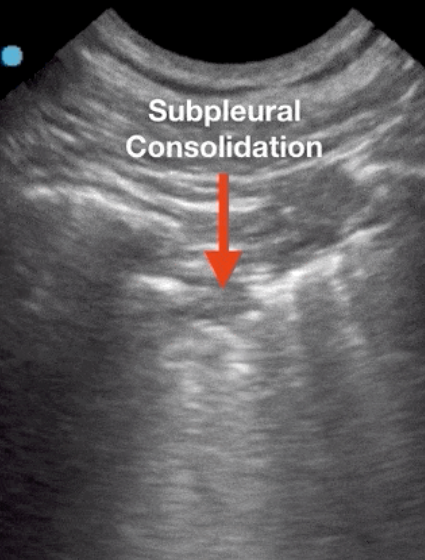

ULTRASOUND PLEURAL SPACE